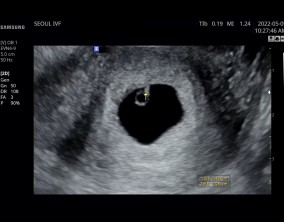

나팔관조영술 하고 인공수정하고 시험관 시술 저는 이렇게 진행했습니다.